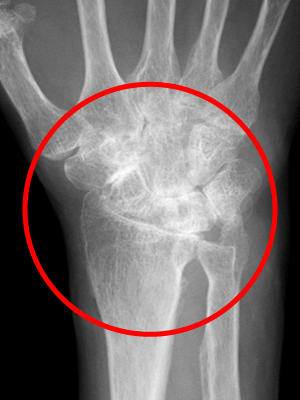

症例2

163歳の女性は、滑膜炎が進行し、関節の腫れや骨の変形が生じ、手の甲の腱が断裂してしまい、薬指や小指をピンと伸ばせない状態になりました。

2手術をして、滑膜の切除と腱の移行を行ったところ、手がきれいに伸びるようになりました。